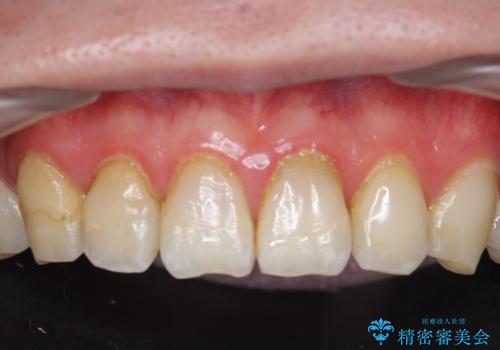

- 右上2、3番目の歯の色・形が気になるといらっしゃった方の症例です。

古い樹脂を除去後、オールセラミッククラウンによる補綴を行いました。